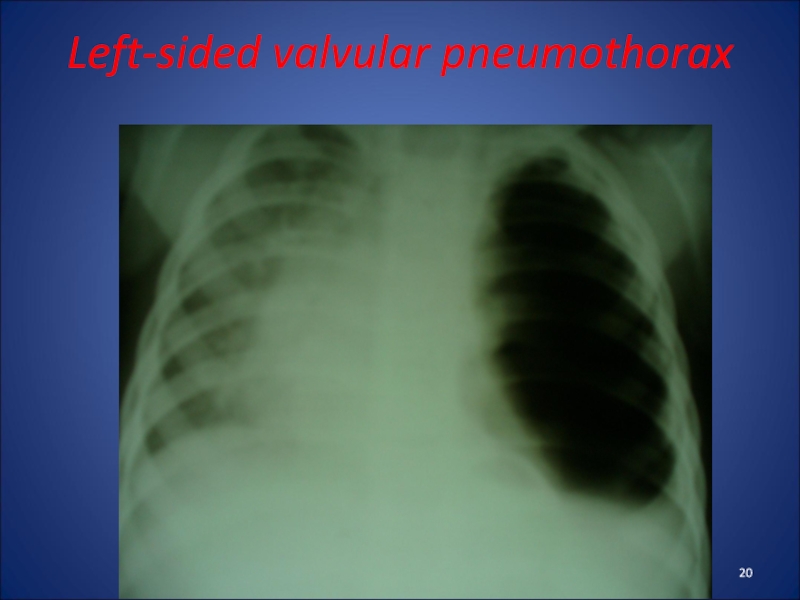

Слайд 20Left-sided valvular pneumothorax

Left-sided valvular pneumothorax

Слайд 19Pneumothorax

- accumulation in the pleural cavity of air that comes

from the damaged lung or bronchus. This compresses the lung.

There are closed, opened and valvular pneumothorax. The most difficult is the valvular pneumothorax, which expresses intrapleural tension.

Clinic: dyspnea, cyanosis, affected half of the chest is not involved in breathing. Percussion - tympanitis, auscultation - weakened breathing on the affected side. There tachycardia may be impaired consciousness.

Radiologically - enlightenment on the affected side, offset shadow of heart to healthy side.

Pneumothorax- accumulation in the pleural cavity of air that comes from the damaged lung or bronchus. This